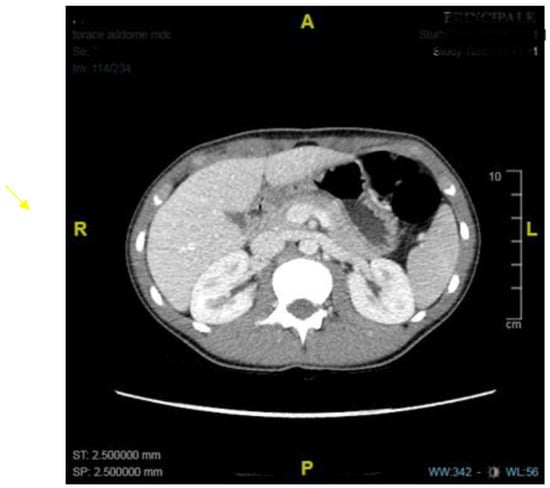

- Plessi, C.; Sica, M.; Molinaro, F.; Fusi, G.; Rossi, F.; Costantini, M.; Roviello, F.; Marano, L.; D’ignazio, A.; Spinelli, C.; et al. Diagnosis and treatment of primary hypertrophic pyloric stenosis (HPS) in older children. J. Pediatr. Surg. Case Rep. 2021, 69, 101860. [Google Scholar] [CrossRef]